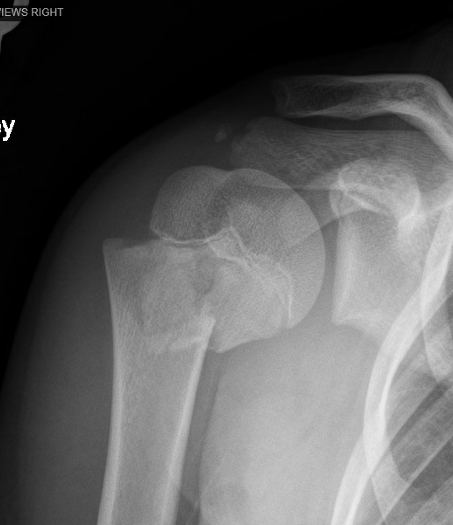

一,肱骨近端骨折的特点:

1,占所有骨骺损伤的3%

2,青少年中更为常见

3,多为Salter-Harris I型或II型损伤

5,可能伴有盂肱关节脱位

Neer-Horwitz分型:

Ⅰ级:移位小于5毫米

Ⅱ级:移位介于5毫米至肱骨干直径的1/3之间

Ⅲ级:移位介于肱骨干直径的1/3至2/3之间

Ⅳ级:移位超过肱骨干直径的2/3